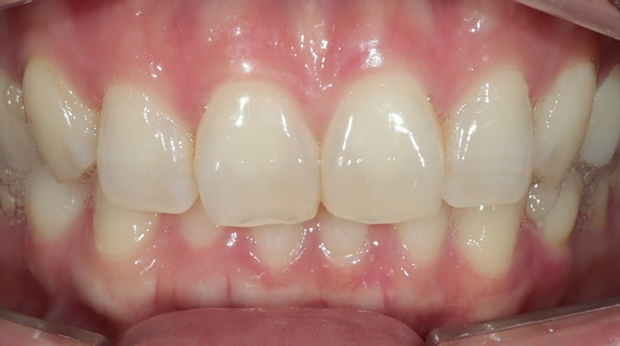

라미네이트